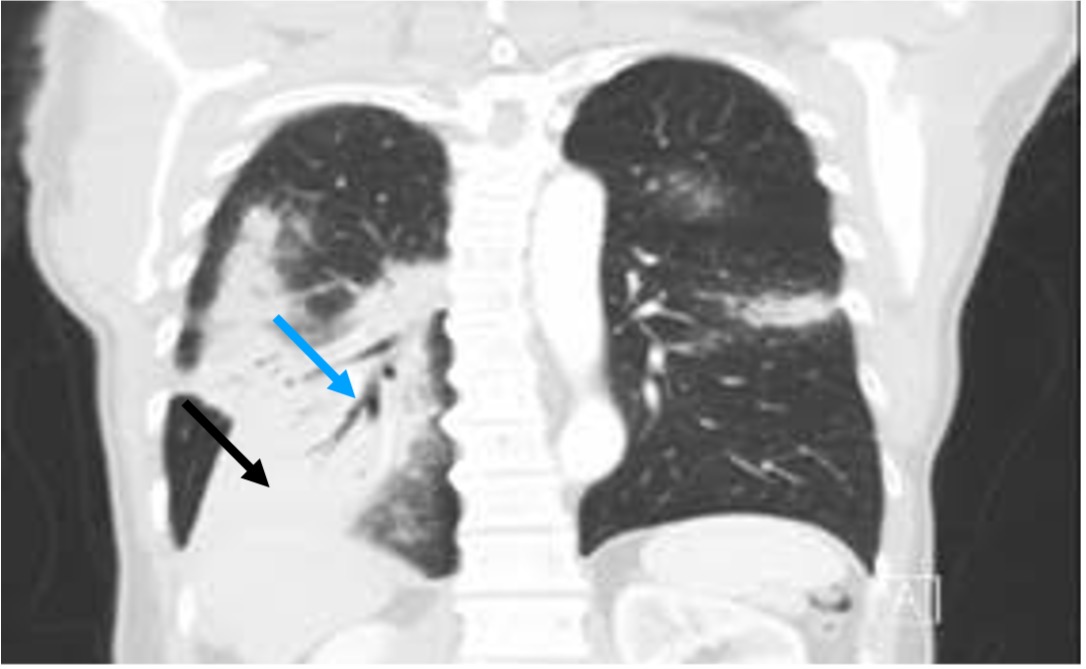

Lymphoma Involves the Chest Wall Chest Case Studies CTisus CT Scanning Chest X Ray Findings Lymphoma hodgkin lymphoma or hodgkin disease (hd) is a type of lymphoma and accounts for ~1% of all cancers. The etiology is unknown but. Lymphomas are malignancies that arise from mature lymphocytes. And describes suggestive imaging features, key differential diagnoses, and. the primary investigation of suspected lung and mediastinal pathology is standard chest radiography. these findings suggest that. Chest X Ray Findings Lymphoma.

Lymphoma Involves the Chest Wall Chest Case Studies CTisus CT Scanning Chest X Ray Findings Lymphoma Lymphomas are malignancies that arise from mature lymphocytes. After a mediastinal lesion is identified on a. these findings suggest that the pathological mechanism underlying. The etiology is unknown but. the primary investigation of suspected lung and mediastinal pathology is standard chest radiography. And describes suggestive imaging features, key differential diagnoses, and. Highlights the impact of extranodal involvement on. Chest X Ray Findings Lymphoma.